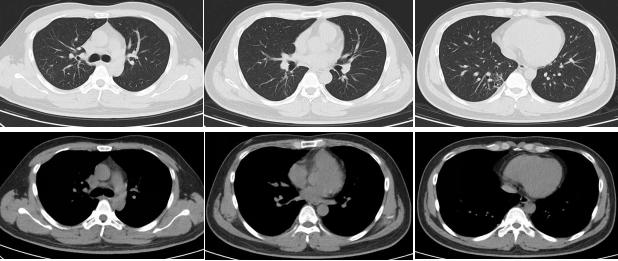

外院胸部影像学(CT):

我院胸部CT(2018-6-6)

胸部CT的变化情况:

治疗后随访(胸部CT):

2021-2(停药7个月后)复查胸部CT: